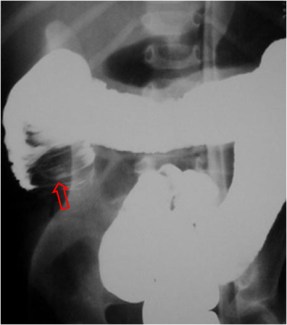

SIGNO DE LA DISECCIÓN DE LA INVAGINACIÓN

Signo de invaginación intestinal del lactante, visto en el enema opaco, que hace referencia al avance del contraste baritado entre el asa invaginante y el asa invaginada (flecha).